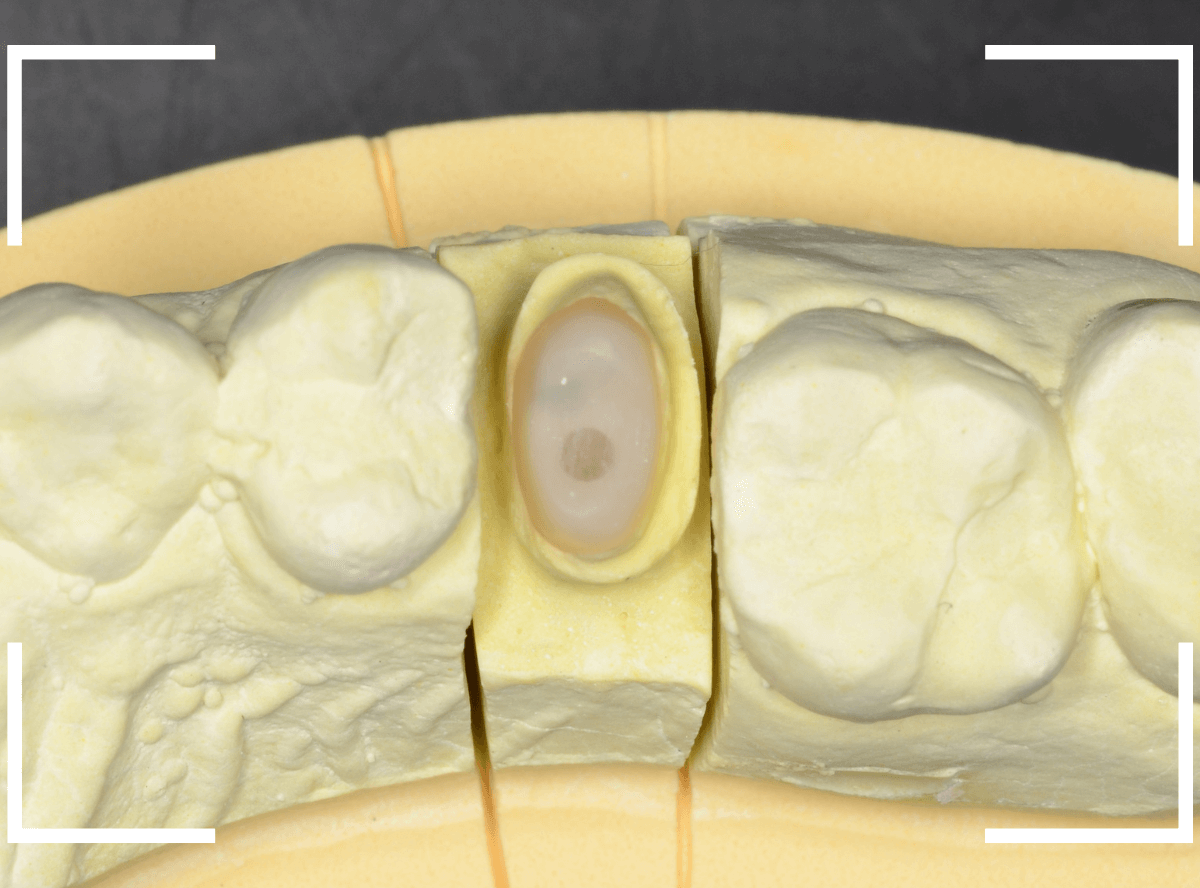

模型上でファイバーコアを製作します。

ファイバーコアをsetし、歯の周りの歯肉が落ち着くまで、仮歯を入れて様子を見ます。

頃合いをみて、歯の型をとってさし歯の製作に移ります。

今回は、オール・ジルコニア・クラウンで製作することになりました。